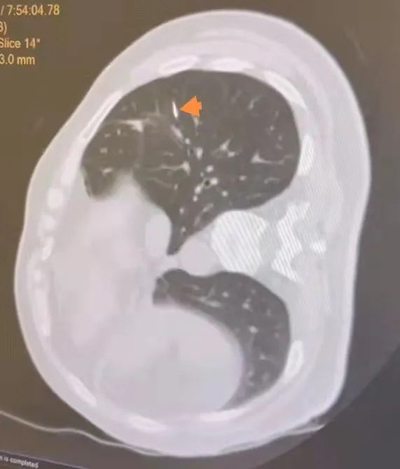

近日,北京积水潭医院胸外科收治一位女性患者, 6月前查体发现肺部结节,位于右肺下叶背段,为3mm磨玻璃结节(GGO),结节无明显实性成分,当时未做治疗,密切随访6月后复查胸部CT,结节进展为5mm结节,GGO伴部分实性成分。

箭头所指即为肿瘤位置